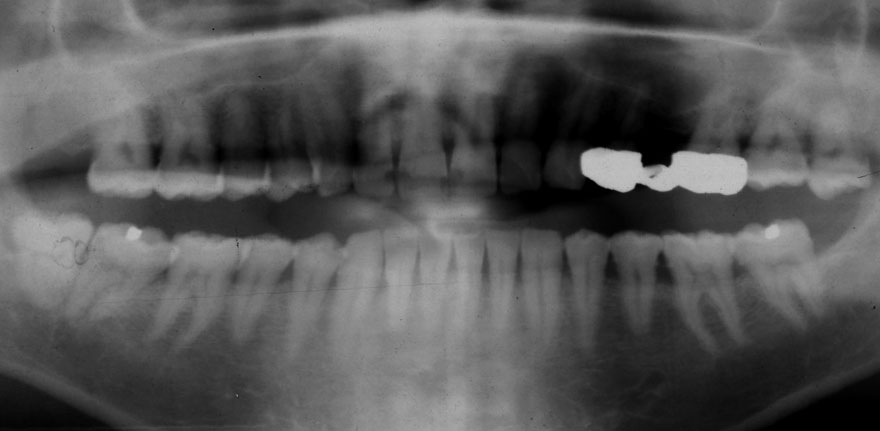

開始年齢 30代

初診時 30歳 女性 平均歯槽骨喪失量:1.46mm

22年後 52歳

平均歯槽骨喪失量:1.55mm

22年間喪失量:-0.09mm

年間喪失速度:-0.004mm

(ケア頻度:1.76ヵ月ごと)